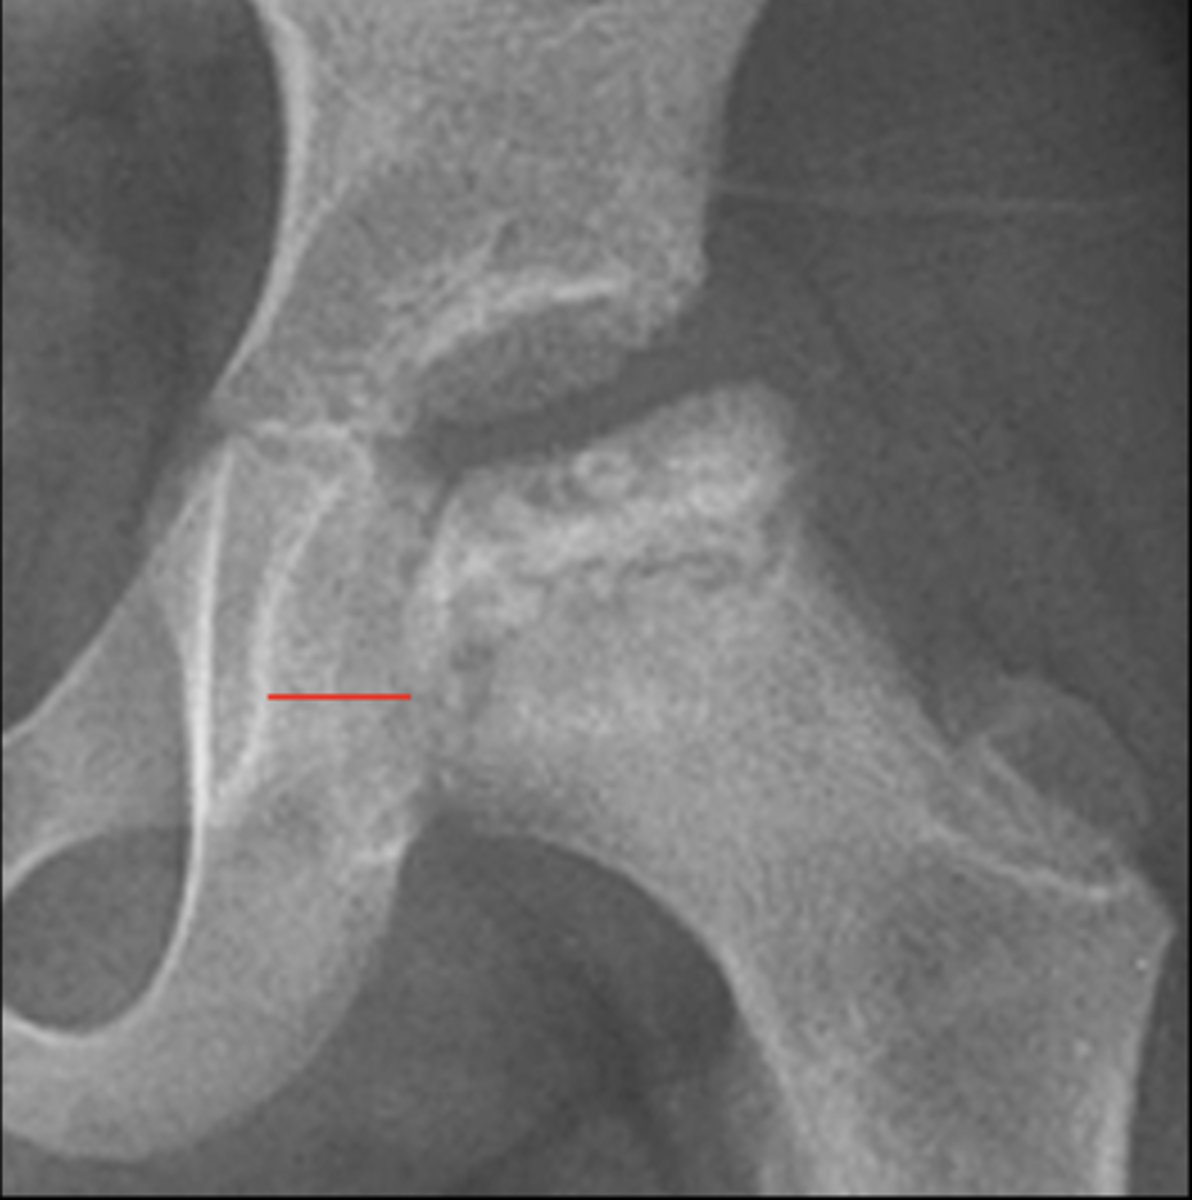

Klein's line

ID measurement

- AP pelvis

- AP hip

Line along femoral neck

Klein's line landmarks

Line should intersect portion of femoral head

Klein's line normal measurement

Slipped capital femoral epiphysis

Clinical significance of Klein's line

Growth plate

A slipped capital femoral epiphysis is a _____ fracture

<p>A slipped capital femoral epiphysis is a _____ fracture</p>